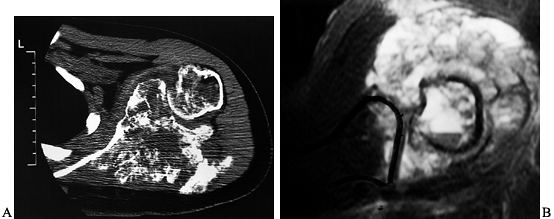

![]() |

Figure 126.24. Tumor involvement of the glenohumeral joint. A:

CT scan of a large osteosarcoma of the scapula, which shows extensive involvement of the soft tissues with involvement of the glenohumeral joint. B: MRI scan of the same area, which shows marked involvement by the tumor surrounding and within the glenohumeral joint (white area, T2 pattern). |